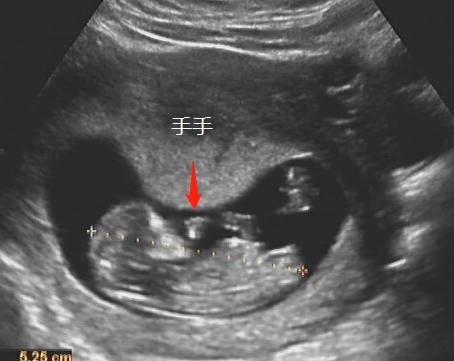

手手脚脚都能看到一些。

上图就是一个两脚朝天,此时我们可以在这个切面观察TA 的股骨长,股骨长的测值也可以作为矫正孕周的一个重要参数。